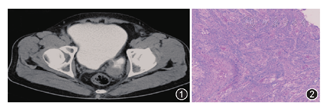

患者,男,59岁,2015年11月11日因排尿不畅伴尿痛2年,肉眼血尿2 d入院。患者入院前5个月曾因排尿不畅伴尿痛行膀胱镜检查,见膀胱左侧壁一直径约2.5 cm憩室,邻近左输尿管开口,当时予保守治疗改善排尿症状。查体:耻骨上区未及明显充盈,深压痛(+)。直肠指检:前列腺Ⅰ°大,质韧,未及结节,无触痛,中央沟变浅,指套无染血。尿常规检查:尿潜血(3+),尿白细胞(3+),尿蛋白(+)。B超检查示前列腺增生伴钙化,膀胱憩室。尿流率检测:最大尿流率14.6 ml/min。盆腔CT检查:膀胱左后方憩室,憩室壁欠规整、增厚(图1)。术前诊断为膀胱憩室伴感染,前列腺增生。全麻下行膀胱憩室切除术+左输尿管膀胱再植术。病理检查:灰白色囊壁样组织,大小约8.0 cm×5.0 cm×0.4 cm,囊内壁光滑,局灶咖啡色。镜下见(膀胱憩室)浸润性低分化尿路上皮癌累及送检膀胱憩室壁全层。于2周后行根治性全膀胱切除术+双侧输尿管皮肤造口术。病理检查:膀胱约8.0 cm×7.0 cm×5.0 cm,膀胱左下壁厚、质硬,切面灰白,质硬区范围4.0 cm×3.0 cm;见完整双侧精囊腺及前列腺,左盆腔淋巴结2枚。镜下见膀胱憩室化生性癌,部分区域为浸润性高级别尿路上皮癌,部分区域为鳞状细胞癌,部分区域为骨肉瘤(图2);癌组织紧邻左侧精囊腺,左输精管及右精囊腺未见癌浸润;前列腺未见癌浸润;左盆腔淋巴结2枚未见癌转移。免疫组化染色检查:CKp(++),CK7(+++),P40(+),CK5/6(+)。术后予辅助盆腔放疗,累计照射5 000cGy/25次,予紫杉醇脂质体+顺铂辅助化疗2个周期。术后随访6个月未见肿瘤复发。